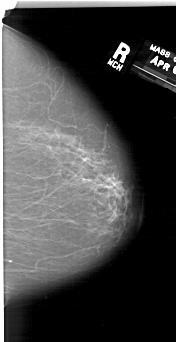

A_1192_1.RIGHT_MLO

RIGHT_CC LINES 6496 PIXELS_PER_LINE 3331 BITS_PER_PIXEL 12 RESOLUTION 43.5 NON_OVERLAY

RIGHT_MLO LINES 6436 PIXELS_PER_LINE 3511 BITS_PER_PIXEL 12 RESOLUTION 43.5 NON_OVERLAY